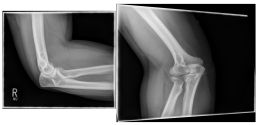

Photo: A fracture with several framents |